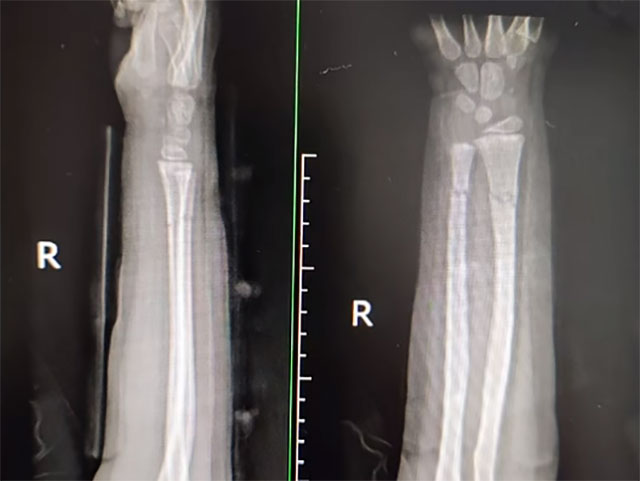

6岁的宇宇在学校玩耍时不慎摔伤右手,家属带其前往就近医院就诊,诊断为尺桡骨双骨折,建议其手术治疗。家属多方打听得知西南医科大学附属中医医院骨伤科创伤·正骨组开展的中医正骨手法复位可以不用手术,便前来就诊。

术前影像

术后复查

仅仅1分钟就完成了骨折复位,宇宇的疼痛明显减轻了,手部畸形也消失了。骨折复位后再外敷上本院中医特色院内制剂,用特制的杉树皮小夹板包扎固定。6周后,骨折愈合,宇宇手部活动自如。

术前

术后

根据骨折与脱位的具体情况,进行骨折手法整复,选好适当的小夹板、绷带、棉垫和束带等材料,充分配合骨伤科特制的中药制剂内服及外用治疗,具有复位过程快、固定效果好、疼痛缓解迅速、康复时间短、治疗费用低等优势。